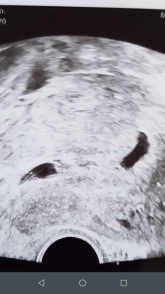

Dobrý deň. Našej NM vložili jedno embryo. Pri hcg 3500 na ultrazvuku nebolo vidieť nič. Podozrenie na mimomaternicové tehotenstvo, našťastie to nebolo. Neskôr na ultrazvuku boli vidieť dve bublinky, ale zase prázdne. Na poslednom kontrolnom ultrazvuku sa v jednej ukázal plod, ale v druhej nie. Je možné, že to druhé nie je GS, ale napríklad hematóm? Alebo ako je to GS, môže sa v ňom ukázať ešte plod?Ultrazvuk spravený podľa poslednej menštruácie 5+5tt.

Dobrý den, v týdnu 5+5 by měl být plod již jasně vidět, takže pokud v 2. gestačním váčku není, pak už by se neměl objevit. Zřejmě se jedná o syndrom mizejícího dvojčete, kdy vznikly 2 gestační váčky, ale jen jeden plod pokračuje ve vývoji.